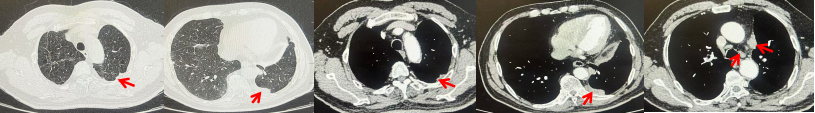

71岁男性,高血压病史20年,口服药物治疗,无糖尿病、心脏病等基础疾病,吸烟史50年,20支/天,已戒1年余,无饮酒史,无肿瘤家族史。2023.11因咳嗽、咳痰行胸CT检查:左肺下叶占位性病变,大小约12mmx8mm(如图5)。2023.11.20行“单孔胸腔镜左肺中下叶切除、肺门及纵隔淋巴结清扫、胸膜粘连松解术”;术后病理:(左肺下叶)结合免疫组化鳞状细胞癌(中、低分化),局部见脉管内癌栓,未见确切神经侵犯,(气管切缘)净。(淋巴结)未见转移癌0/19(4组0/1;5组0/1;6组0/2;7组0/1;9组0/1;10组0/2;11组0/3;12组0/2;13组0/2;14组0/4)。术后分期pT1bN0M0 IA期,术后定期复查。

2024.09.12复查胸部CT示左侧胸膜结节,大者约为27mmx13mm,考虑转移可能性大,纵隔淋巴结增大,恶性?(如图6)。患者行胸膜穿刺活检取病理,结果示(胸膜)结合免疫组化,支持鳞状细胞癌,PD-L1(克隆号28-8)TPS约20%。分期为rT0N2bM1a IVA期,DFS为10个月。2024.09.24起行替雷利珠单抗联合紫杉醇+卡铂方案治疗4周期,复查胸CT评效SD(如图7)。后患者因脑梗塞停止治疗,于综合医院就诊,后未返院复查及治疗。

图5:患者手术前(2023.11)胸部CT肺窗及纵隔窗

图6:患者胸膜及纵隔转移(2024.09)胸部CT肺窗及纵隔窗

图7:替雷利珠单抗联合白蛋白紫杉醇+卡铂治疗4周期后(2024.12)胸部CT肺窗及纵隔窗